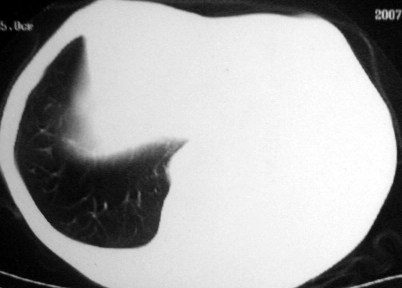

男,54岁,咳嗽,气喘半年,胸痛一月.

血性胸水

左侧胸腔积液 斜裂积液 心包积液 左肺不张 考虑左肺ca并胸膜心包转移。

支持左肺下叶中心型肺癌(累及舌叶)伴阻塞性肺炎、膨胀不全、胸腔积液、心包少量积液。

考虑左肺下叶中央型肺癌伴阻塞性肺炎及肺不张,纵隔受累可能,胸膜转移。